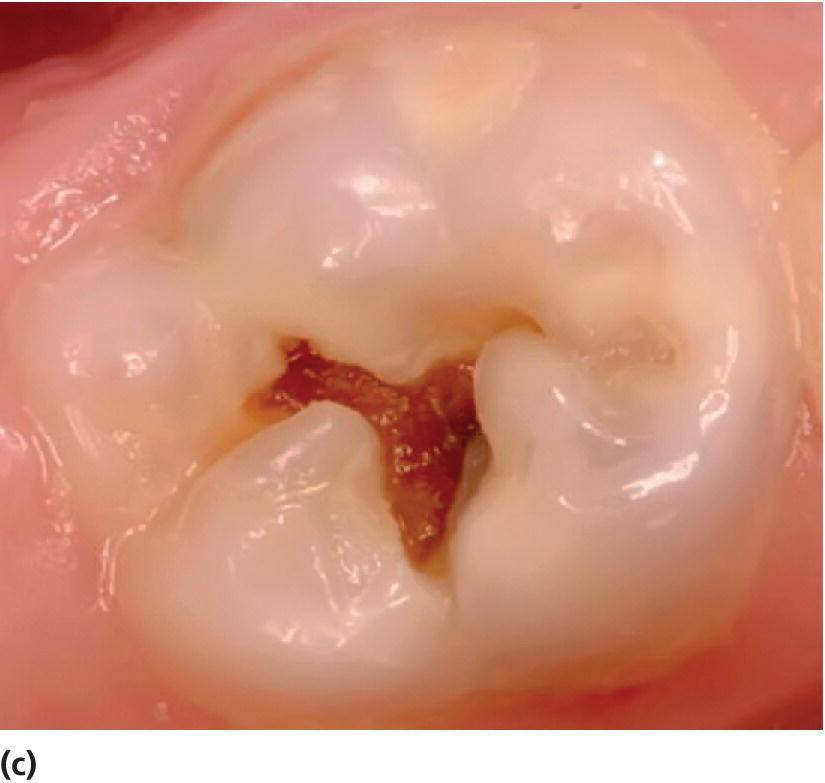

Acute Caries

Acute Caries Dental Caries Lesions The management of dental caries should be aimed at 1) detecting initial lesions, 2) determining caries activity, 3) performing a caries risk assessment, 4) preventing new. The symptoms—tender, painful teeth—appear late. The american dental association recognizes early childhood caries (ecc) as the presence of one or more decayed, noncavitated or cavitated. The international caries detection and assessment system (icdas) serves. Dental Caries Lesions.

Caries lesions on the occlusal surface of molar tooth Download Scientific Diagram Dental Caries Lesions The symptoms—tender, painful teeth—appear late. The ada science & research institute, working with an expert panel convened by the ada council on scientific affairs, has developed a clinical practice guideline on restorative. The american dental association (ada) council on scientific affairs convened a panel of general, pediatric, and public health dentists specializing in cariology, operative dentistry, and dental materials to. Dental Caries Lesions.